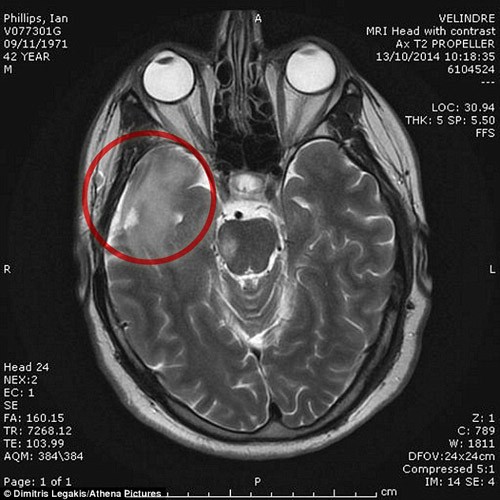

Các bác sĩ đã tìm thấy khối u có kích thước như quả chanh trong đầu Ian.

Sau khi đến bệnh viện với một cơn đau đầu khủng khiếp, Ian Phillips - một doanh nhân người Anh, đã nhận được kết quả chẩn đoán khá tồi tệ. Theo kiểm tra sơ bộ, các bác sĩ cho biết Ian có một khối u to bằng quả chanh ở trong não và họ tuyên bố rằng thời gian sống sót của anh chỉ còn kéo dài được khoảng 3 năm nữa.